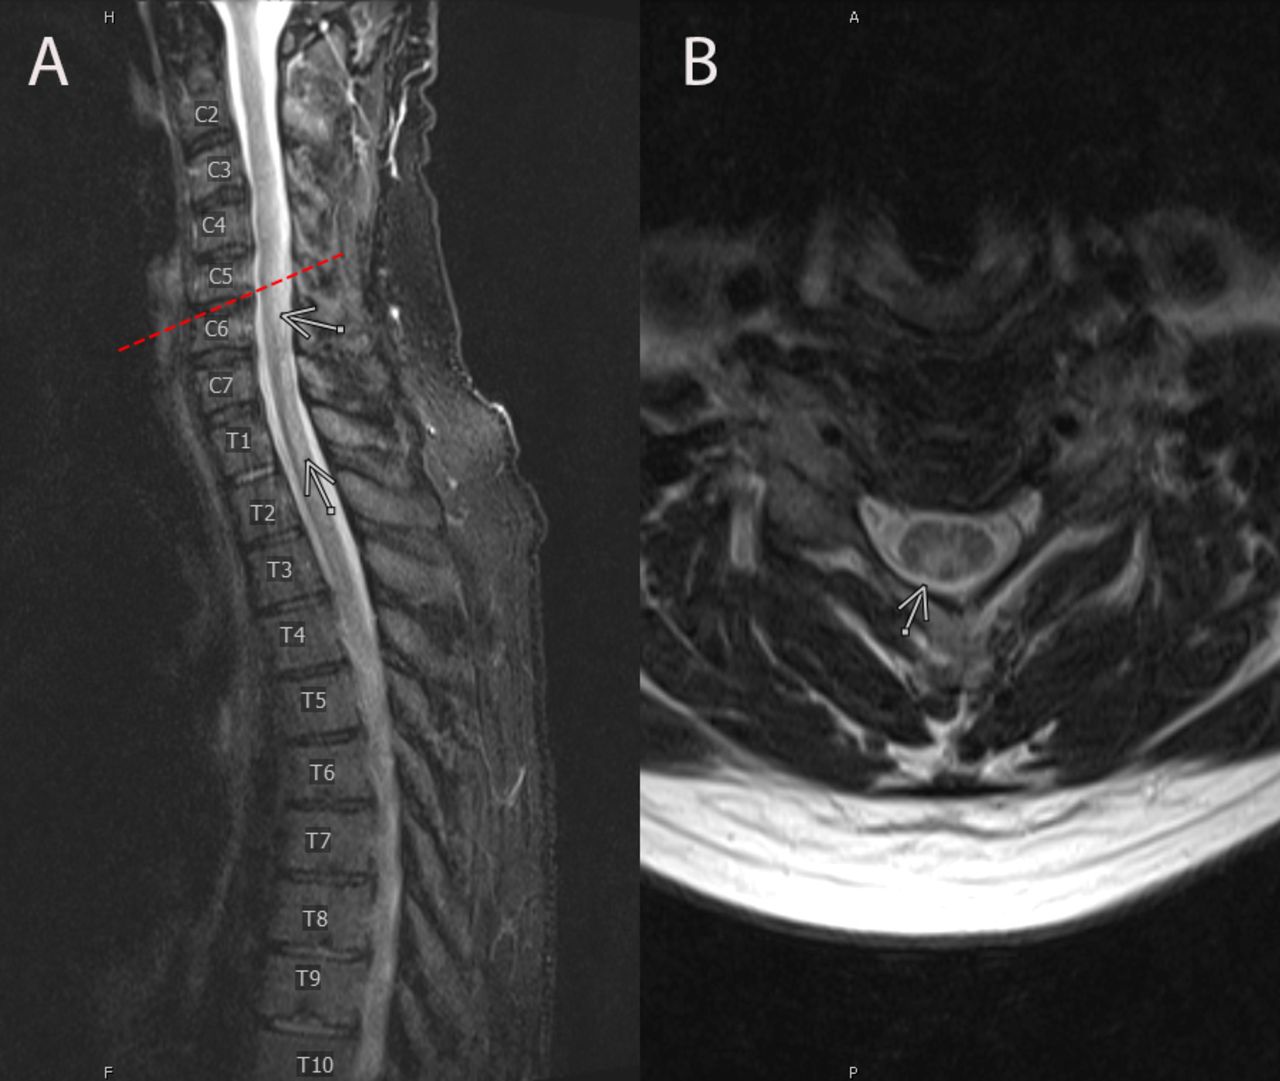

Learn about Subacute Combined Degeneration of the spinal cord, a serious neurological condition often linked to vitamin B12 deficiency. Discover the primary symptoms, underlying causes, and effective treatment strategies for this demyelinating disease. Understanding these diagnostic signs and early interventions is essential for preventing permanent nerve damage and restoring long-term neurological health.

Read full article: Combined Subacute Degeneration